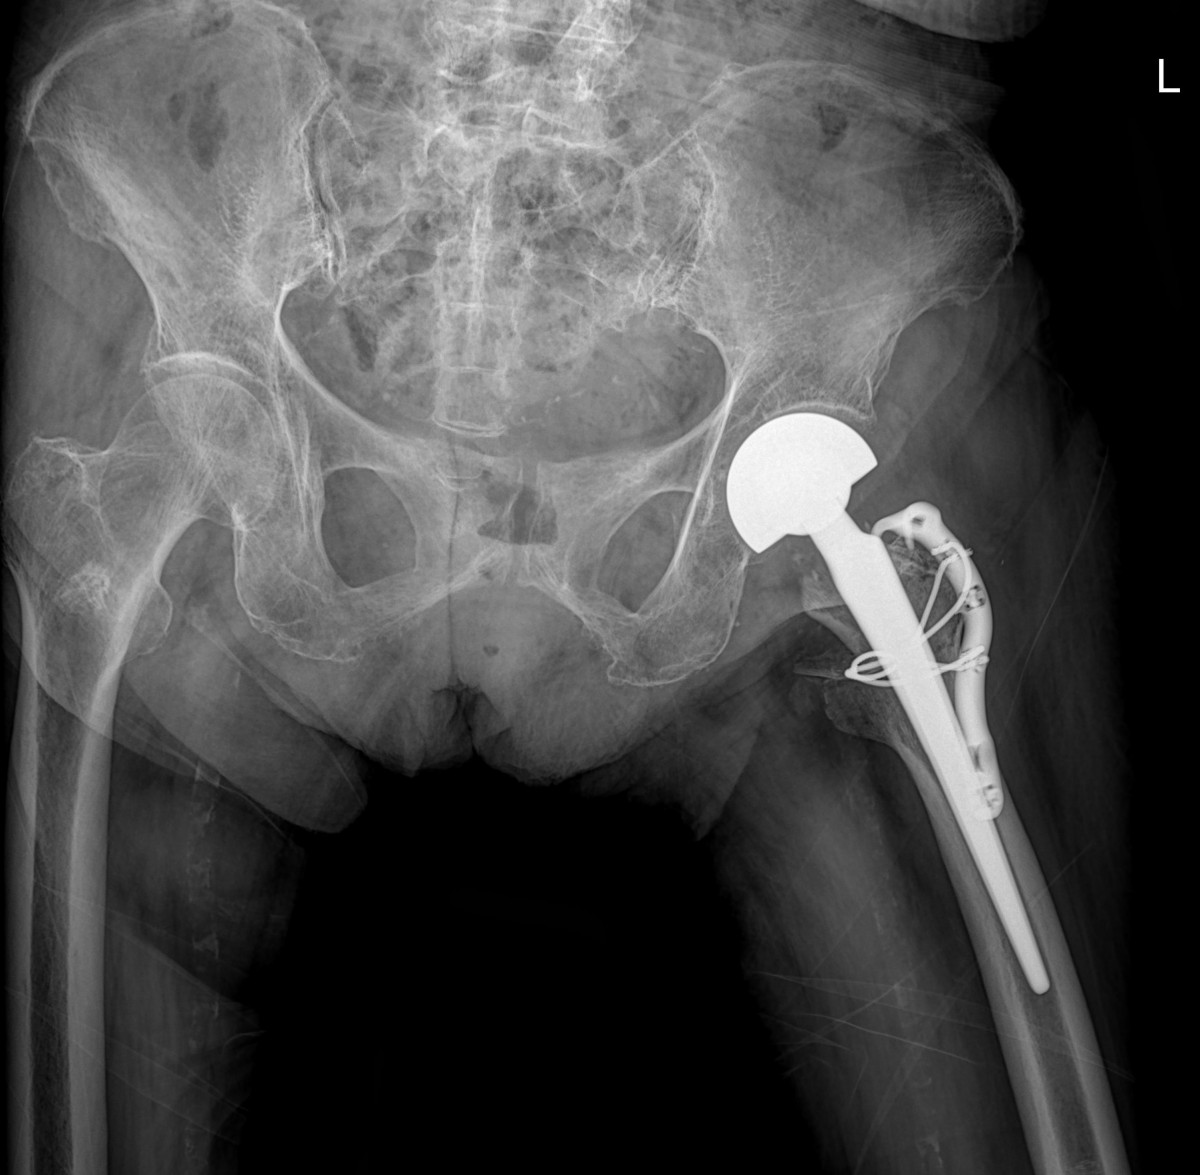

이재상원장님 대퇴골 인공관절 치환술 이경O 환자

작성자 최고관리자 댓글 0건 조회 1,657회 작성일 24-07-06 11:33

a5bb5aa2c868c534dc48e760e3eaf4b4_1720233216_6989.jpg

a5bb5aa2c868c534dc48e760e3eaf4b4_1720233230_127.jpg